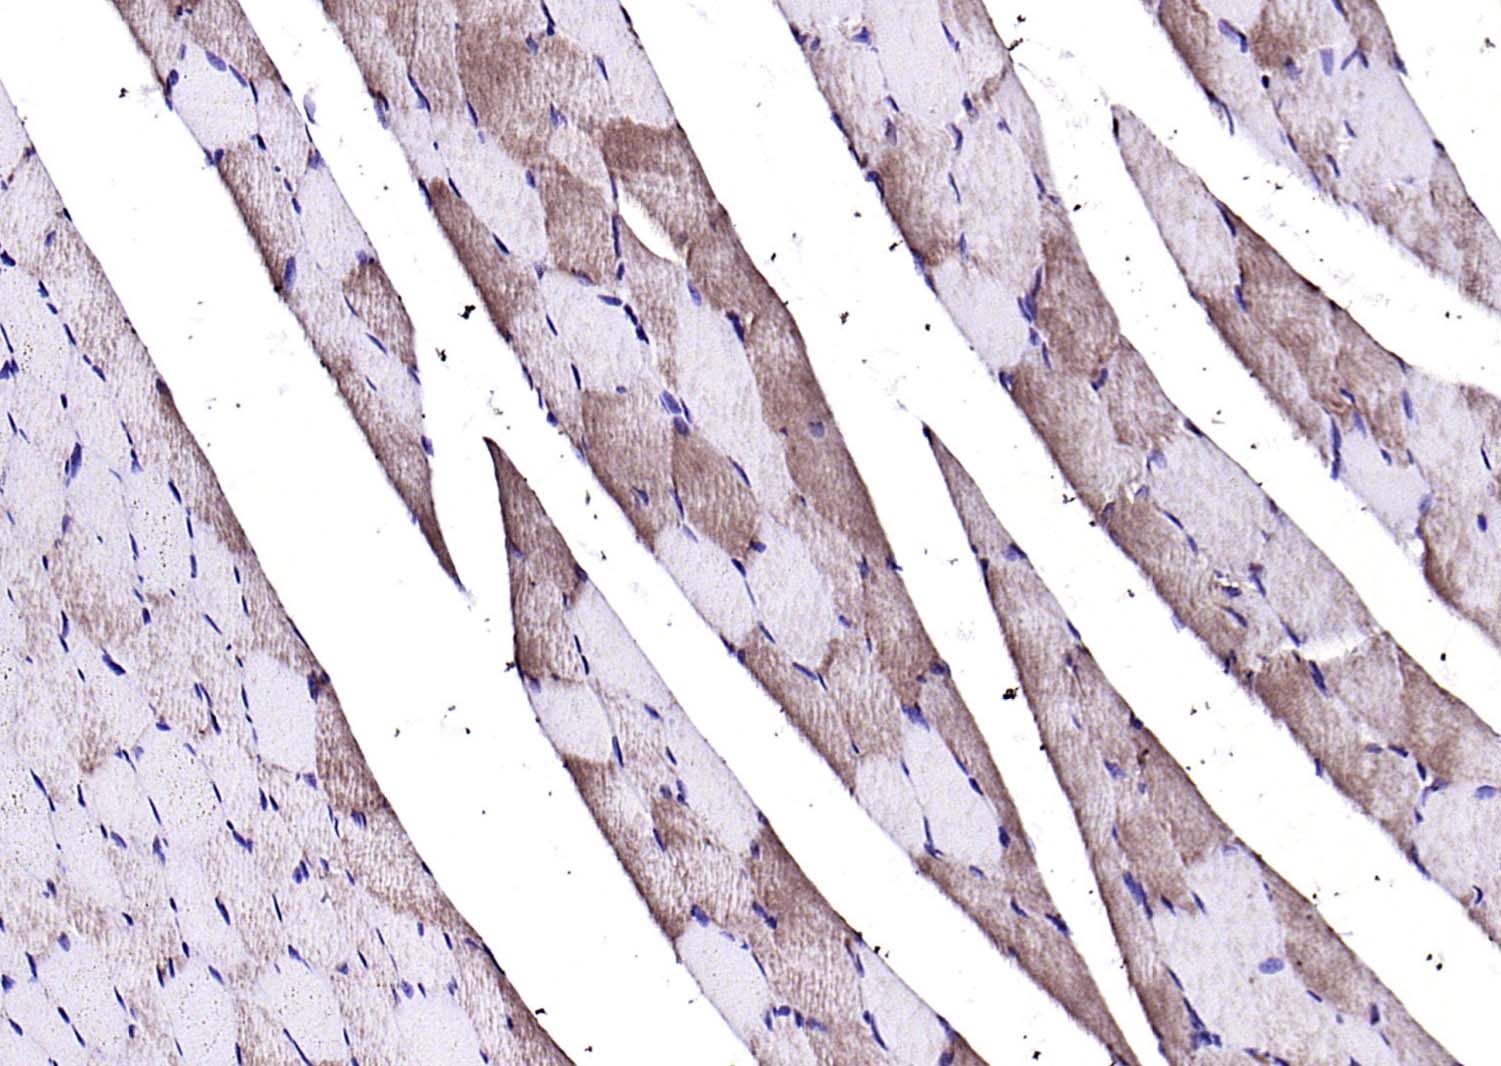

Paraformaldehyde-fixed, paraffin embedded (rat skeletal muscle); Antigen retrieval by boiling in sodium citrate buffer (pH6.0) for 15min; Block endogenous peroxidase by 3% hydrogen peroxide for 20 minutes; Blocking buffer (normal goat serum) at 37°C for 30min; Antibody incubation with (Calmodulin 1/2/3) Polyclonal Antibody, Unconjugated (bs-3666R) at 1:200 overnight at 4°C, followed by operating according to SP Kit(Rabbit) (sp-0023) instructionsand DAB staining.